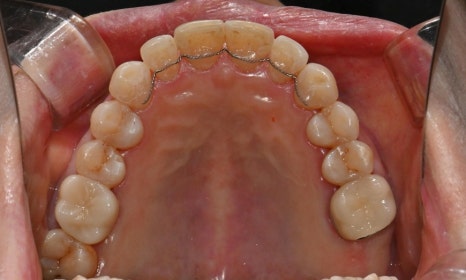

본 환자는 70세 여환으로 가만히 입을 다물고 있을 때 화난 것 처럼 보인다고 해서 튀어나온 앞니를 조금 넣고 싶다는 주소로 내원하셨습니다. 전체적인 치아 및 잇몸 상태를 검진해본 결과, 마모되어 깨진 치아도 있었고, 치경부(치아와 잇몸 사이 경계 부위)가 마모되어 파여 있는 부위도 많았습니다.

2025.2.3. 초진

교정 치료를 시작하기 전에 위아래 깨진 어금니는 보철 치료를 시행하였고, 치경부는 레진 치료를 시행하였습니다. 거의 뿌리의 신경관 근처까지 파여있던 치아가 치경부 레진 치료로 자연스럽게 수복이 되었습니다.

치경부 레진 치료 전후